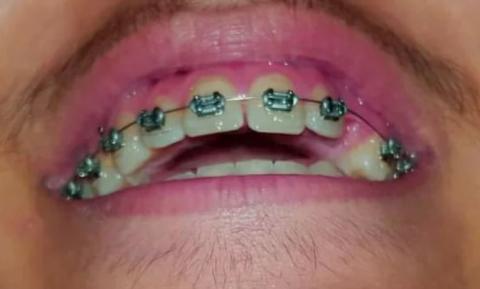

Dental Case Analysis: Lower Arch With Braces and Multiple Carious Lesions

The image shows the lower dental arch with fixed orthodontic brackets in place. Several posterior teeth exhibit dark cavitated areas, consistent with active dental caries. Oral hygiene challenges are evident around brackets and molars.